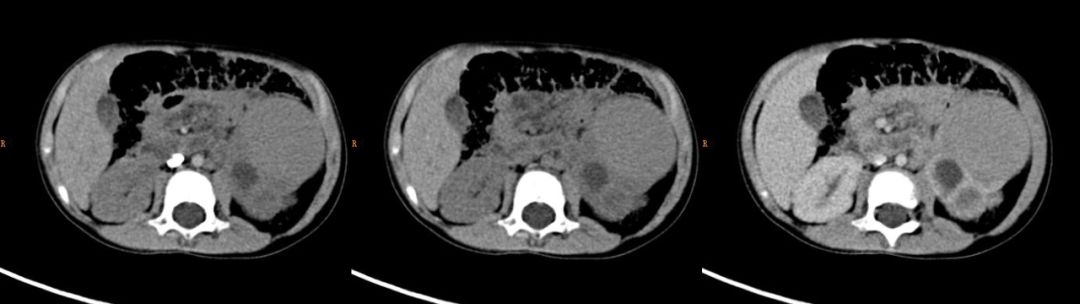

肾透明细胞肉瘤(CCSK)。男,4 岁。可见肿瘤液性成分较多,多发椎体(箭)、胸骨和肋骨(未列出)转移。儿童肾肿瘤伴骨转移时首先考虑肾透明细胞肉瘤。

男,8 个月。右肾区巨大占位伴点状钙化灶。实性部分中度强化,强化实性部分与液化坏死区呈现黑白相间虎斑样条纹改变。伴有肺转移(未列出)。